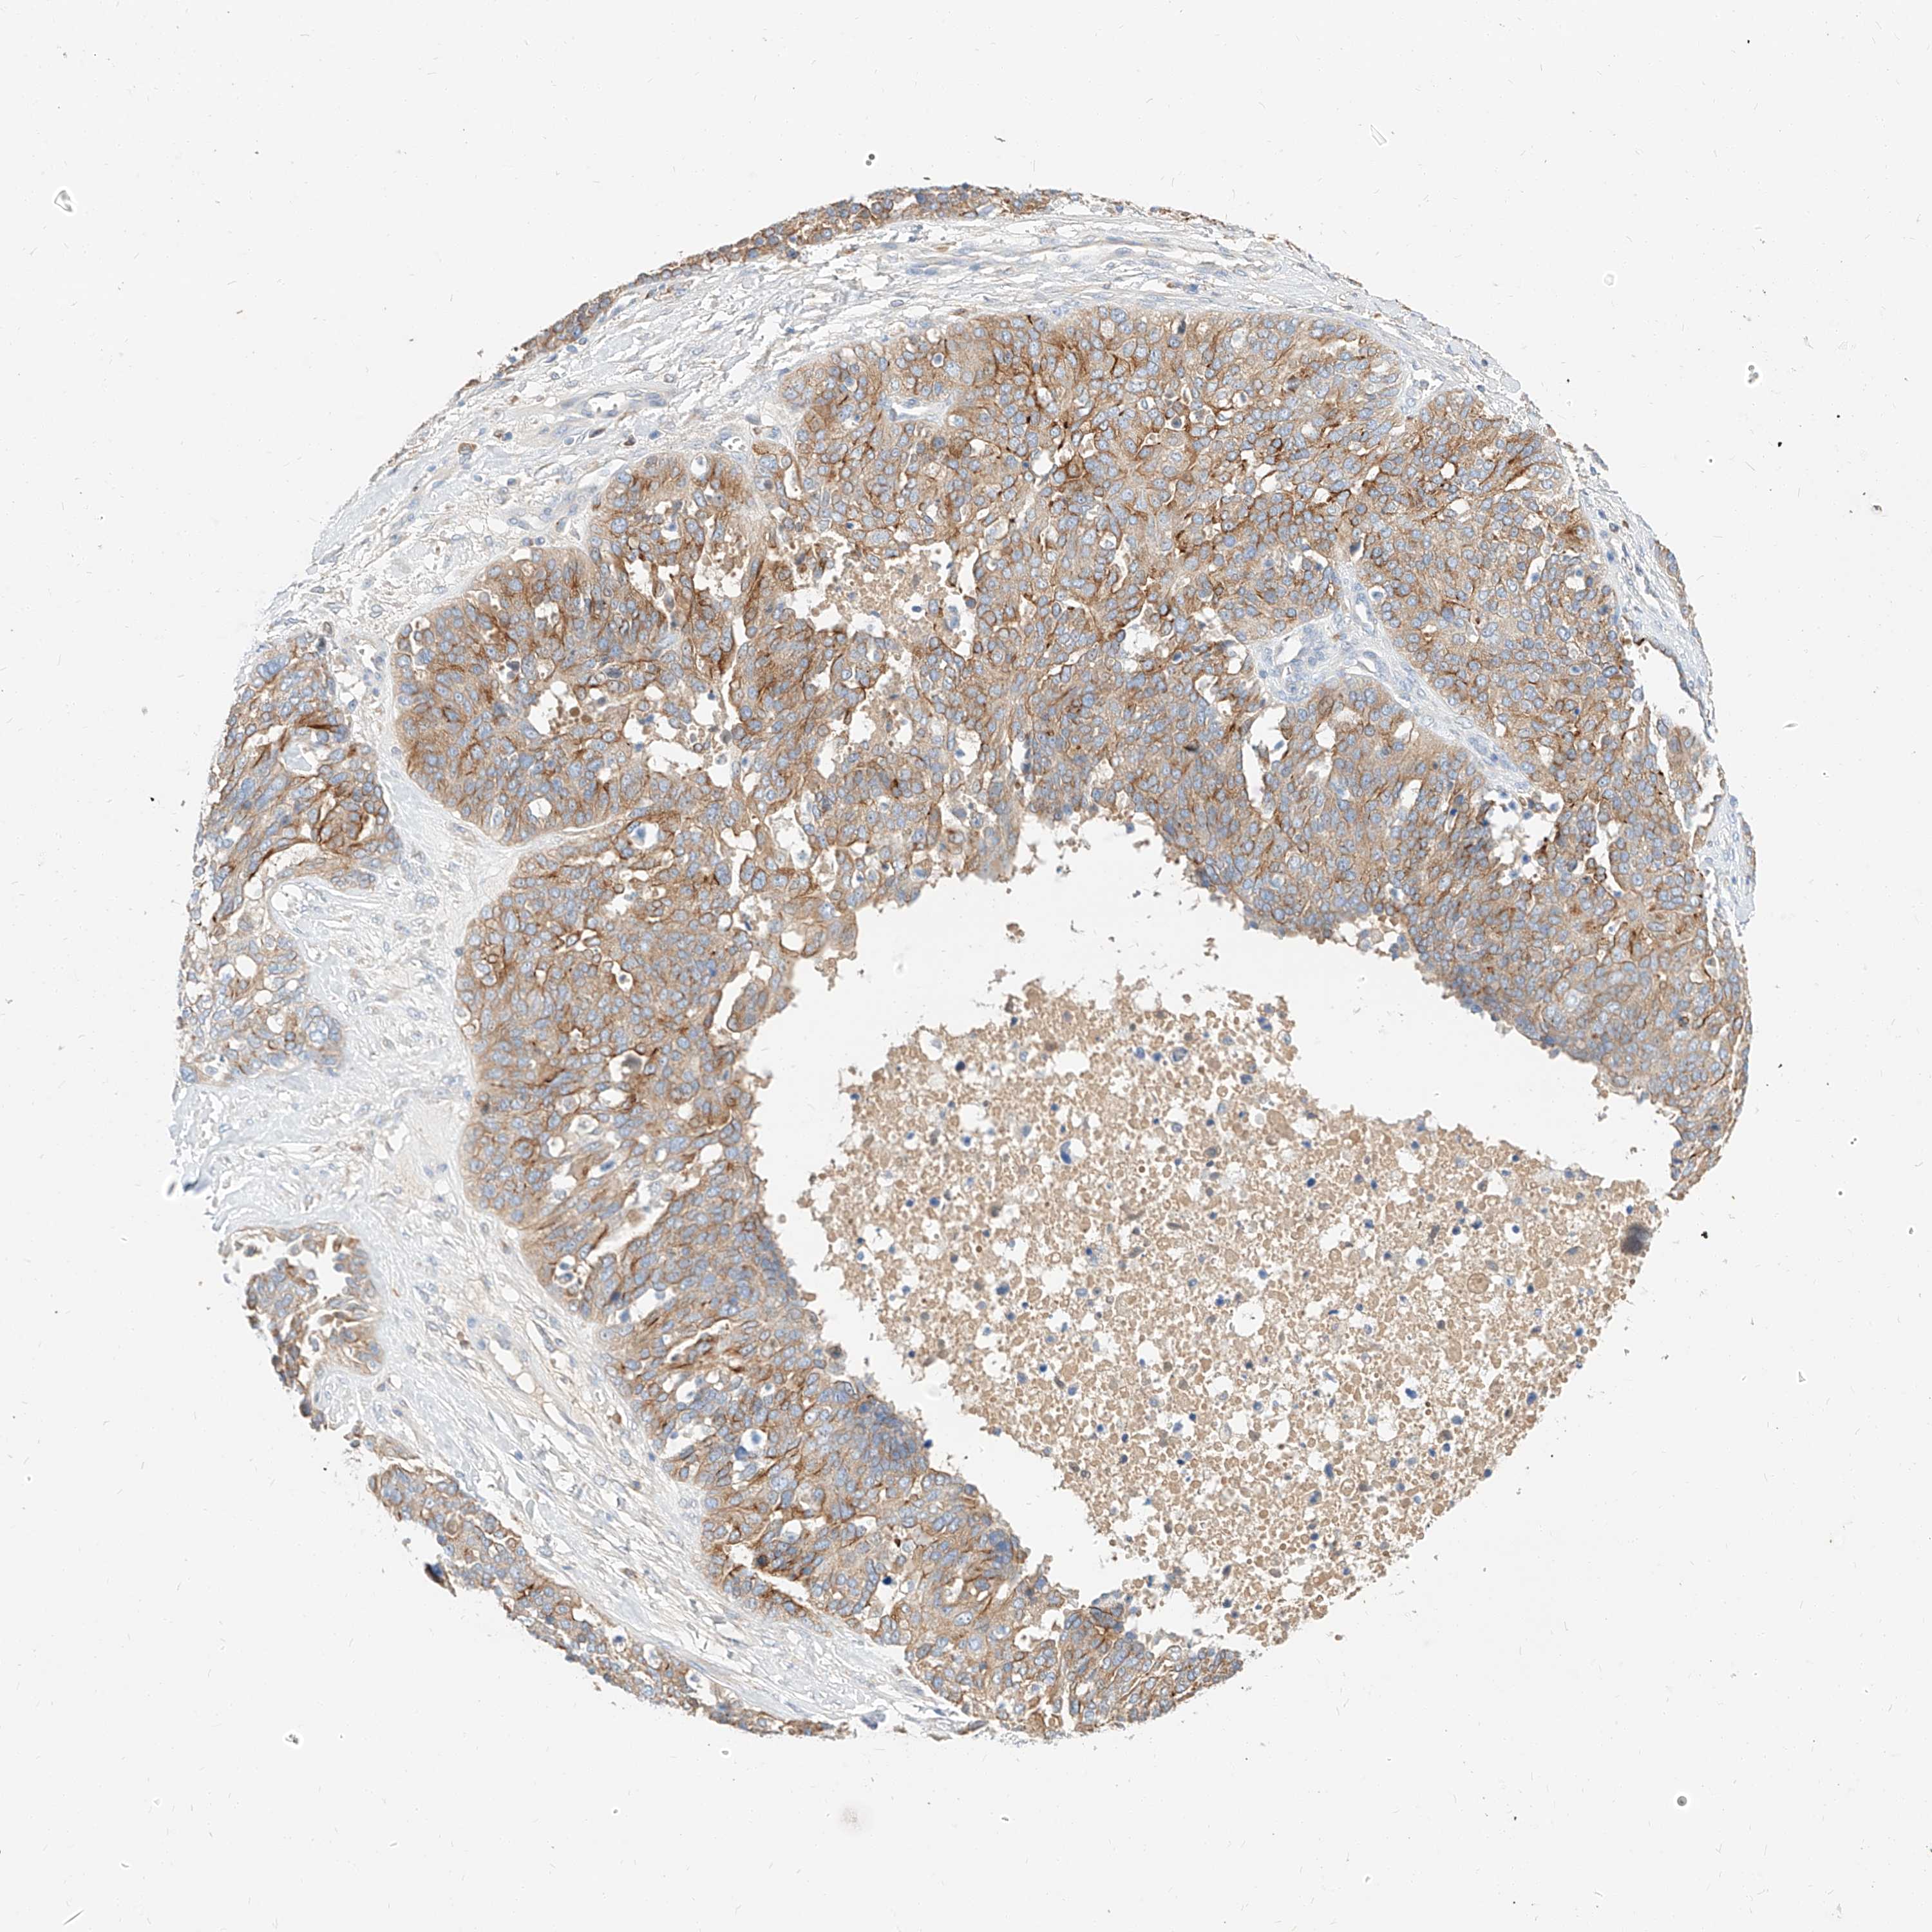

OVARIAN CANCER - Protein expressioni

A mouse-over function shows sample information and annotation data. Click on an image to view it in a full screen mode. Samples can be filtered based on level of antibody staining by selecting one or several of the following categories: high, medium, low and not detected. The assay and annotation is described here.

Note that samples used for immunohistochemistry by the Human Protein Atlas do not correspond to samples in the TCGA dataset.

Antibody stainingi

Antibody staining in the annotated cell types in the current human tissue is reported as not detected, low, medium, or high, based on conventional immunohistochemistry profiling in selected tissues. This score is based on the combination of the staining intensity and fraction of stained cells.

Each image is clickable and will lead to virtual microscopy that enables deeper exploration of all samples and also displays staining intensity scores, fraction scores and subcellular localization as well as patient and tissue information for each sample.

Antibody HPA029712

Antibody HPA029713

Cystadenocarcinoma, serous, NOS

Carcinoma, endometroid

Cystadenocarcinoma, mucinous, NOS

Carcinoma, NOS